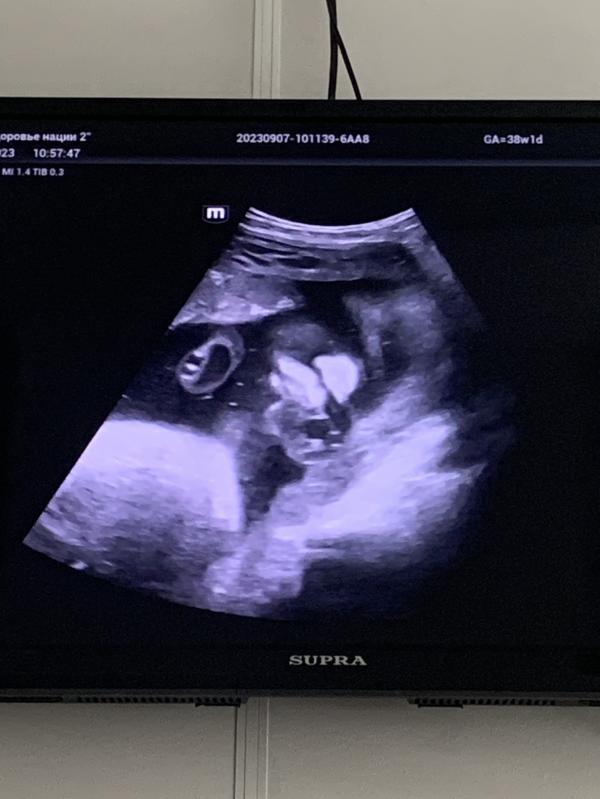

Сходила на УЗИ, симфизита нет. Прострелы у меня оттого, что головка очень-очень низко. Это же значит, что скоро роды?) Или ничего не значит?😄 Пробка, кстати, отошла ещё 1,5 недели назад.

Человечек в 38 недель весит ~3500🙈 сын на 40й неделе родился 3120, а принцесса будет пухляшом)) видимо, бесконечные булочки и конфеты во 2м триместре сыграли свою роль.

Ребёнок полностью сформирован и готов к родам, движения датчика по животу не оценила - хмурилась, потом вообще отвернулась😄